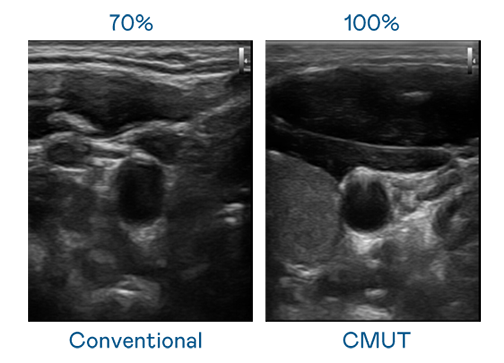

CMUT 技术是一种用电容式微机电元件来产生超音波讯号的技术。与传统 PZT 压电式技术相比,CMUT 频宽增加 30%,更宽频的超音波讯号让影像解析度大幅提升,是实现高影像品质医疗超音波扫描、促进精准医疗发展的关键技术。

大频宽带来超清晰影像

超音波影像的解析度高低,首先取决于探头能发出的讯号频宽。6008集团 CMUT 可提供高清晰的超音波讯号,提供高频宽、高灵敏度、影像纹理细节更高的超音波影像,协助医护人员缩短影像判读时间及利用精准的医疗影像进行诊断。